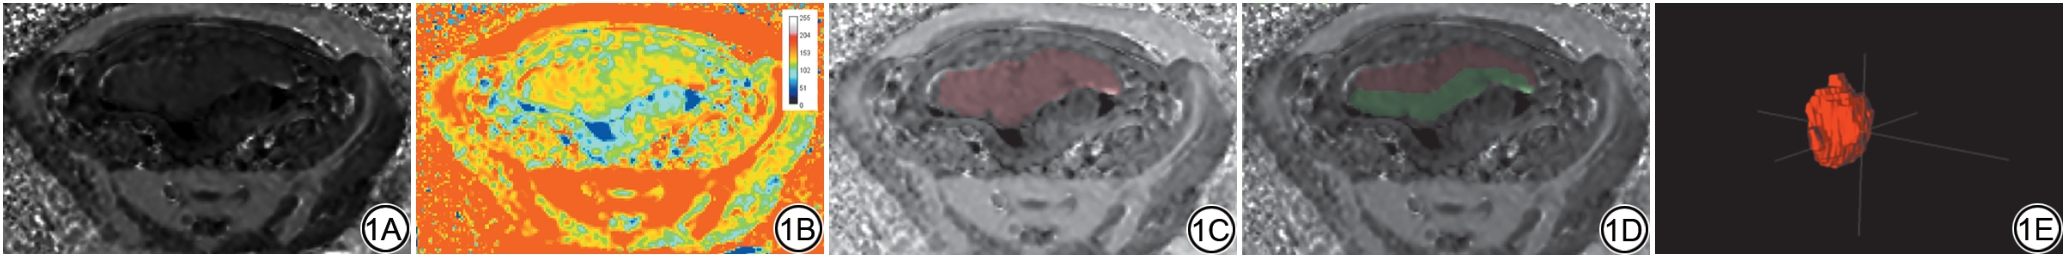

由2名具有10年以上腹部放射诊断经验的主治医师将vMRE、sADC和ADC图导入ITK-SNAP软件(v4.0, Penn Image Computing and Science Laboratory, USA)后采用双盲法对整个胎盘、整个胎盘母体侧和胎儿侧进行三维感兴趣区(volume of interest, VOI)勾画(图1),并提取胎盘μdiff、sADC、ADC参数、整体胎盘体积(volume, VOL)及胎盘最大厚度(thicknessmax, THKmax)。胎盘母体侧和胎儿侧的勾画是按胎盘所在层面对胎盘均分逐层进行勾画,勾画过程中如遇到边界不清或结构不明确的区域,由一位工作20年以上的主任医师进行确认后勾画。

图1  胎盘虚拟剪切模量图像及感兴趣区勾画示意图。1A:胎盘轴位虚拟剪切模量(μdiff)原始图;1B:胎盘轴位虚拟剪切模量(μdiff)伪彩图;1C:整体胎盘轴位勾画区域(红色区域);1D:胎盘母体-胎儿侧轴位勾画区域(红色区域表示母体侧,绿色区域表示胎儿侧);1E:整个胎盘三维感兴趣区。

Fig. 1  Images of the placenta virtual shear modulus (μdiff) and schematic diagram of regions of interest delineation. 1A: Original image of the axial virtual shear modulus (μdiff) of the placenta; 1B: Pseudo-color image of the axial virtual shear modulus (μdiff) of the placenta; 1C: Axial delieation area of the whole placenta (red area); 1D: Axial delineation area of placenta on the maternal and fetal compartment (the red area indicates the maternal compartment, the green area indicates the fetal compartment); 1E: A volume of interest of the whole placenta.